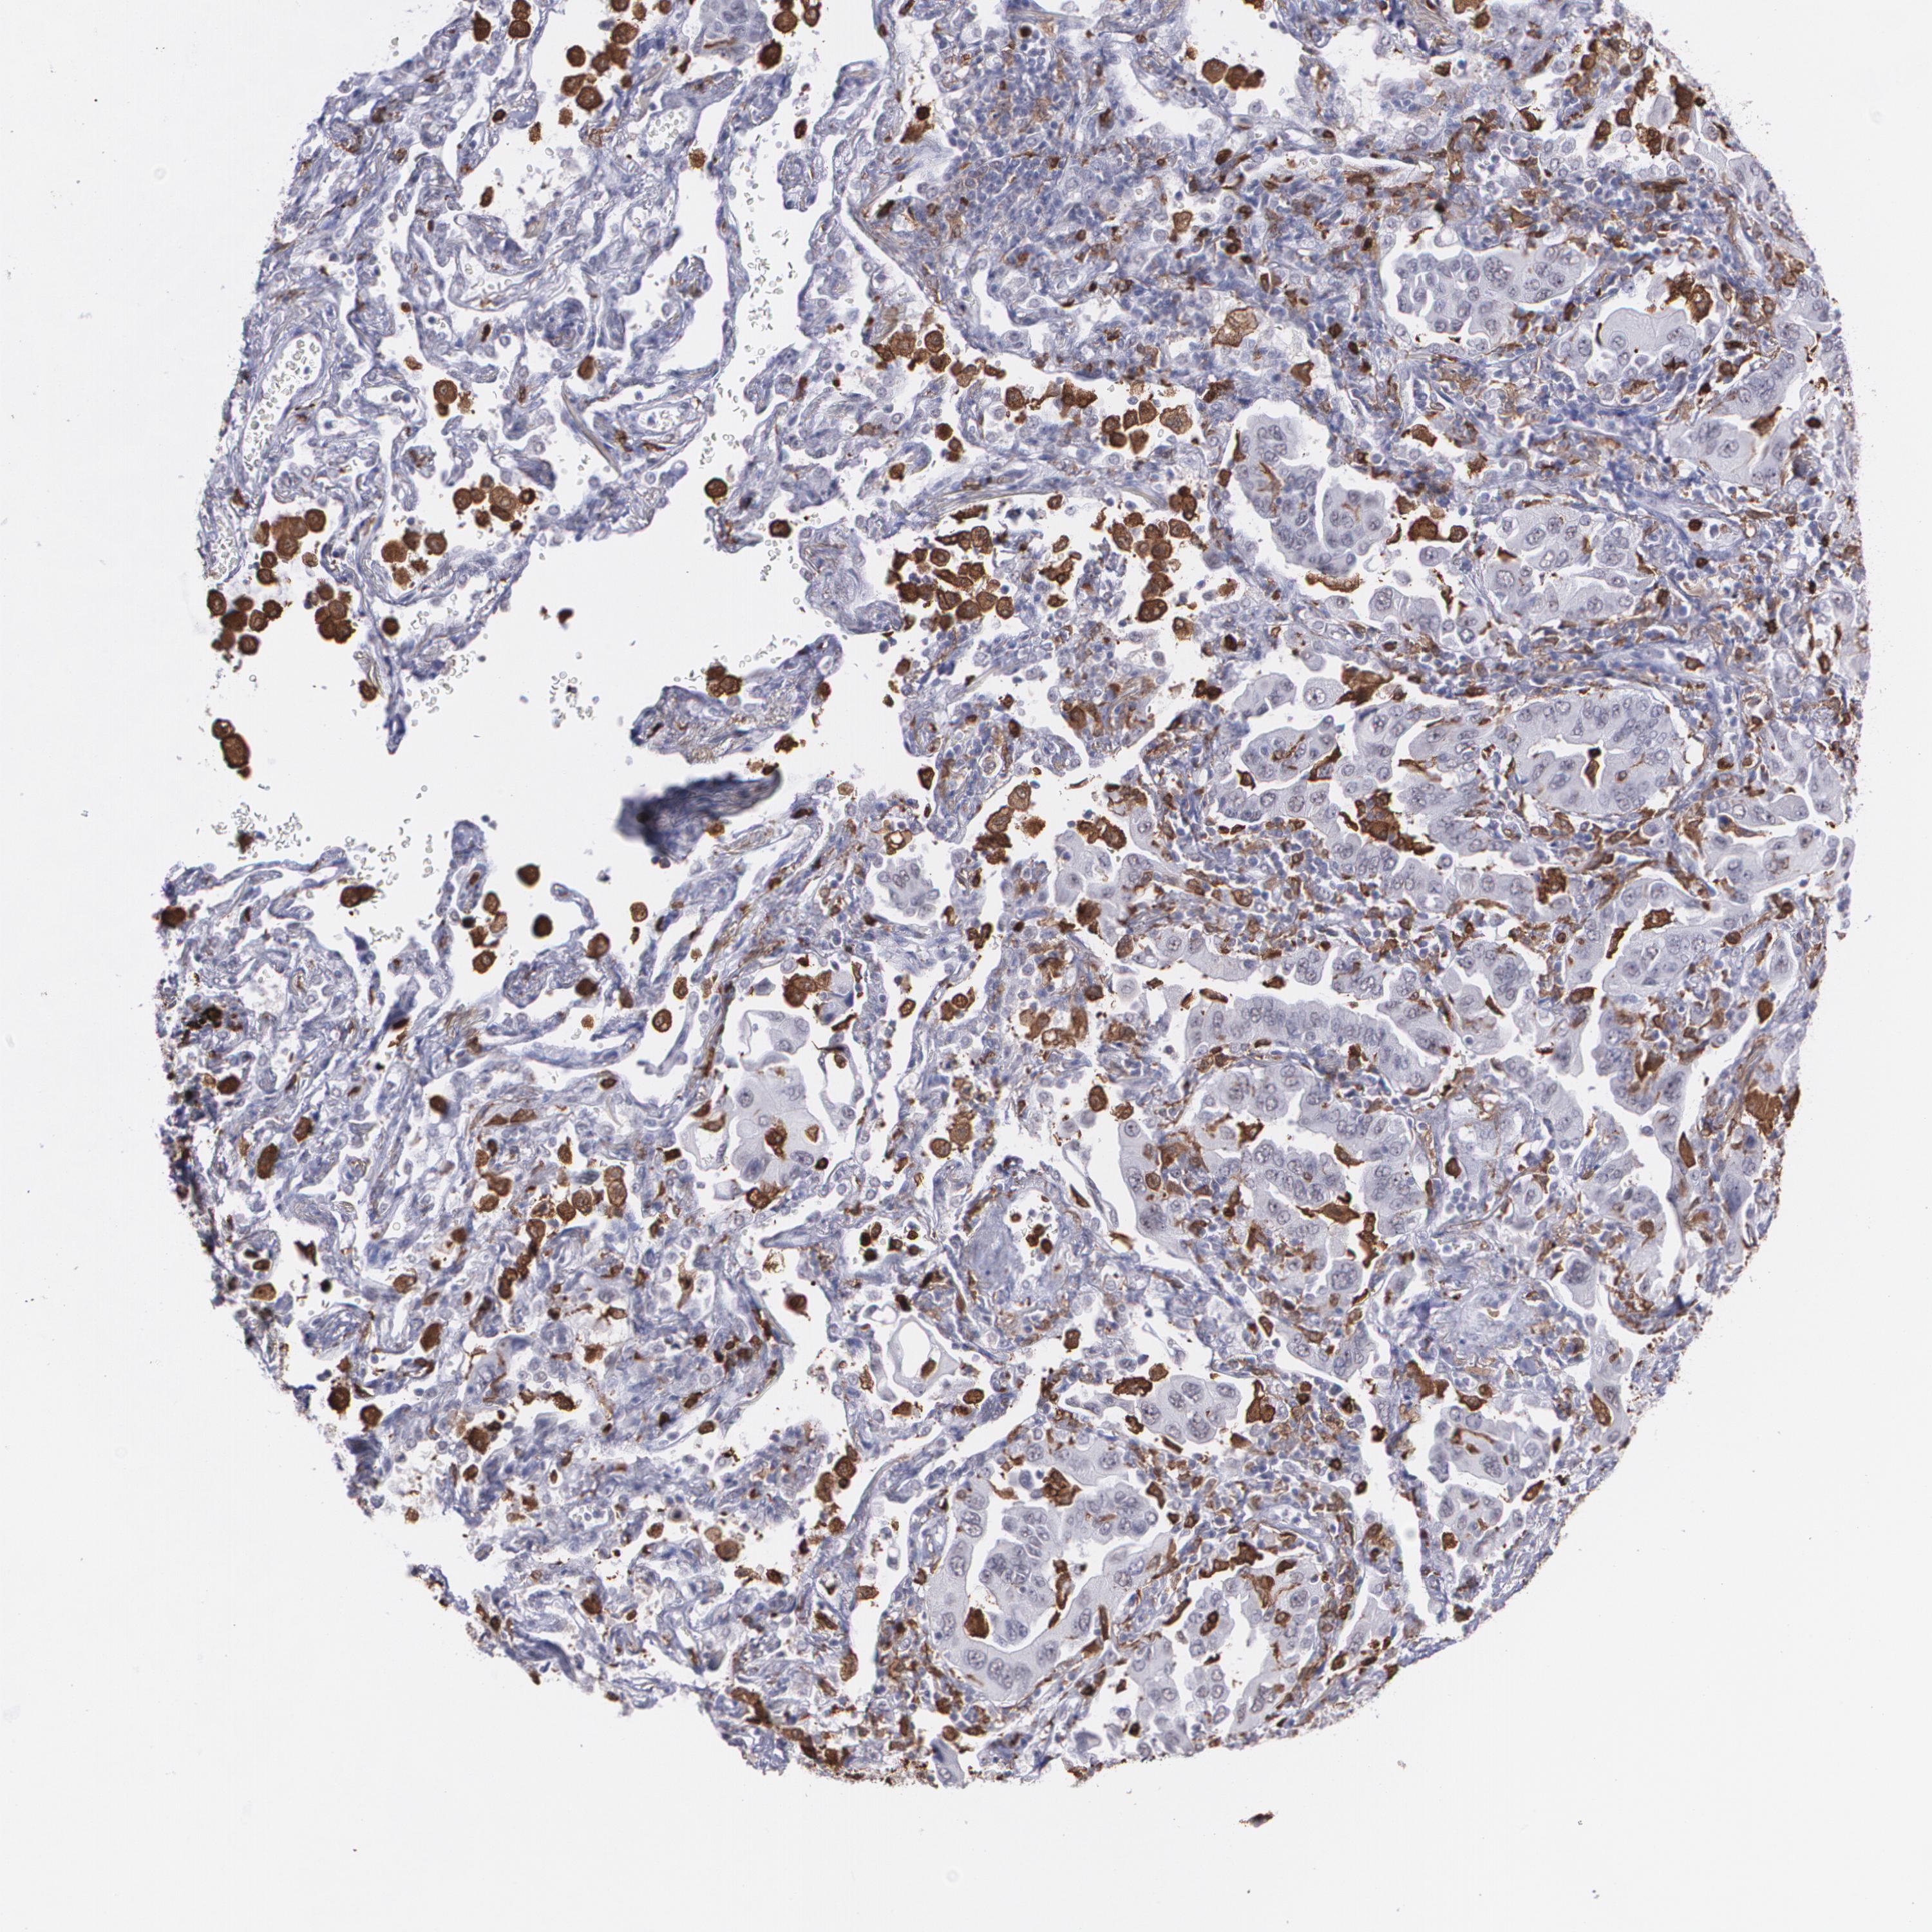

CANCER LUNG CANCER Show tissue menu

LUAD TCGA LUAD VALIDATION LUSC TCGA LUSC VALIDATION PROTEIN LUAD CPTAC PROTEIN LUSC CPTAC PROTEIN EXPRESSION